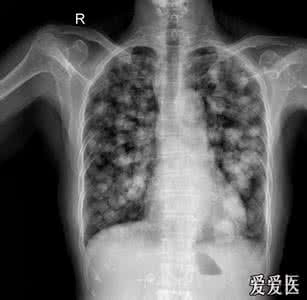

肺部结节症状

1状和体征视其起病的缓急和累及器官的多少而不同。胸内结节病早期常无明显症状和体征。

时、有咳嗽,咳少量痰液,偶见少量咯血;可有乏力、发热、盗汗、食欲减退、体重减轻等。病变广泛时可出现胸闷、气急、甚至发绀。